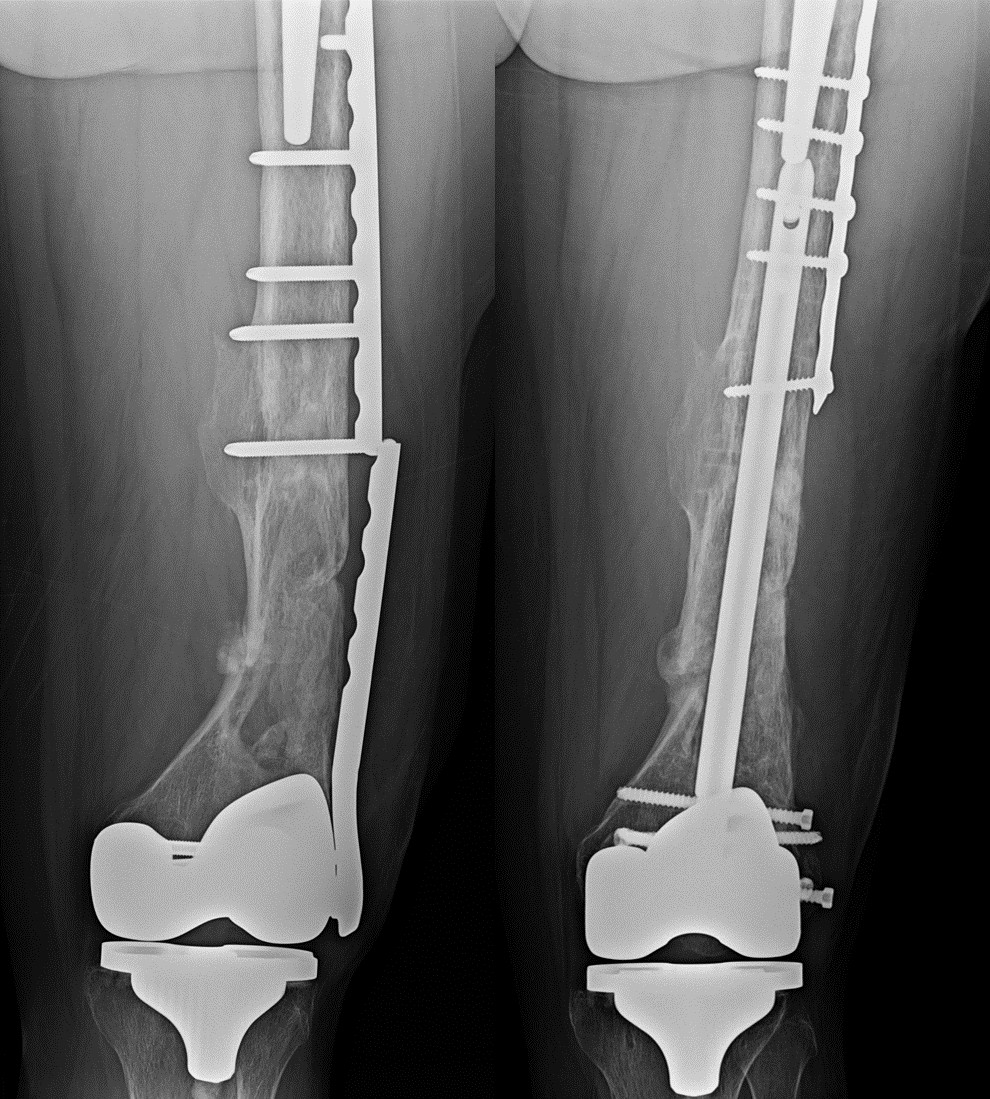

- Intramedullary nailing – A rod is inserted into the bone marrow canal

- Plates and screws – Used for more complex or angled fractures

- Hip replacement – Often done for femoral neck fractures in older adults